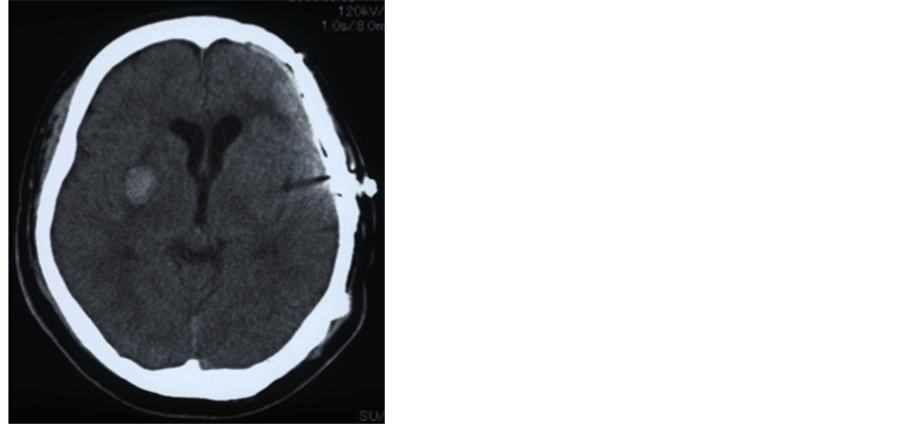

About 25 months after SAH, he was admitted to our hospital for cranioplasty using a custom-made hydroxyapatite (HAP) ceramic implant. On admission, he was clinically obese (body mass index: 34.9) and he had a past history of hypertension and smoking until the onset of SAH. On physical examination and CT scan, a depressed area was located on the temporal part of the skull, but he had no neurological findings (Figure 2). We performed cranial reconstruction surgery using a custom-made HAP ceramic implant (Figure 3). No intraoperative fabrication was needed, and there were no tenting sutures to the reconstructed dura mater. No intraoperative complications, such as injury to the dura, occurred. On the day after the operation, a putaminal hemorrhage was on the opposite side on CT scan (Figure 4). However, there were no physical or neurological findings. Compared to preoperative findings, depression of brain substance in the left frontal lobe and temporal lobe had improved, and the frontal horn of the lateral ventricle was slightly deviated to the left. No adverse events occurred in the postoperative course, and he was discharged from the hospital two weeks after surgery. Follow-up CT scan performed 20 days after surgery showed that the intracerebral hematoma was completely absorbed and the deviation of the frontal horn of the lateral ventricle was improved (Figure 5). Six months after cranioplasty, his skull retained a good shape (Figure 6), and he is keeping in a good course for more than two years postoperatively with no subsequent issues.

Figure 4. CT scan image on the day after the operation, which showed a putaminal hemorrhage on the opposite side of the surgical site.